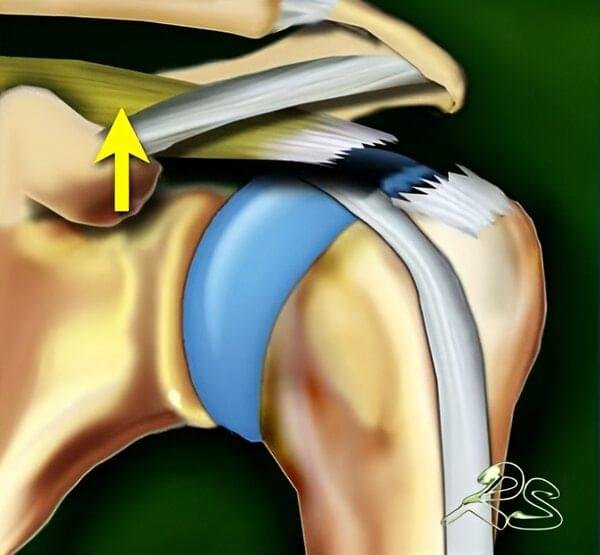

In addition to enabling arm movement, the rotator cuff muscles have an even more important role — stabilizing the humeral head within the glenoid during motion. When stabilization is inadequate, the humeral head may shift upward toward the acromion during arm elevation. This can lead to irritation and injury of the shoulder tendons and bursae.

Bone spurs, particularly those located on the underside of the acromion, can contribute to the development of shoulder impingement syndrome. During arm elevation, the tendon may rub against the bone. If this impingement becomes chronic, it leads to increased tendon wear and may ultimately result in a rotator cuff tear.

The damage occurs on the upper (bursal) side of the tendon, which is in contact with the subacromial bursa. These tears are less common than intrasubstance tears and articular-sided tears. They are often associated with shoulder impingement, where the tendon rubs against the undersurface of the acromion during shoulder movement. The presence of bone spurs (osteophytes) on the inferior surface of the acromion is considered a risk factor, as they may mechanically irritate the tendon. - Articular-sided tear

The main purpose of X-ray imaging is to rule out other causes of shoulder pain, such as arthritis. In massive rotator cuff tears, the humeral head may lose stability and migrate upward toward the acromion (cranial migration), which can be clearly seen on X-ray images.